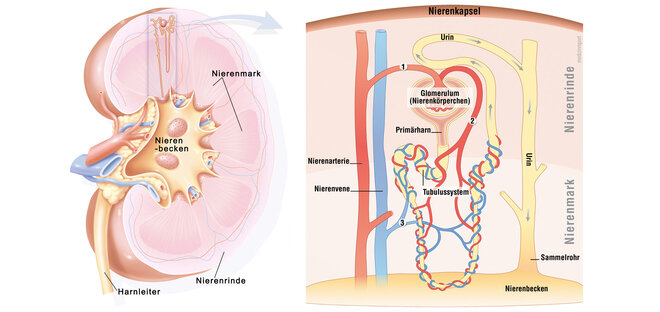

Bei der Glomerulonephritis handelt es sich um eine Entzündung der Nierenkörperchen (Glomeruli). Die Nierenkörperchen bestehen aus einer Art Gefäßknäuel in der Nierenrinde (siehe auch Hintergrundinformation weiter unten), in denen der sogenannte Primärharn gebildet wird. Unterteilt werden die Glomerulonephritiden in eine primäre oder sekundäre Glomerulonephritis. Handelt es sich um eine Entzündung der Nierenkörperchen, ohne weitere Systemerkrankung spricht man von einer primären Glomerulonephritis, ist die Entzündung dagegen Folge einer anderen Erkrankung außerhalb der Nieren, handelt es sich um eine sekundäre Glomerulonephritis.

Bei einer Nierenentzündung können aber auch die Harnkanälchen (Tubuli) und der sie umgebende Raum (Tubulointerstitium) entzündet sein, dann ist von einer tubulo-interstitiellen Nephritis die Rede. Als Folge davon treten Störungen in der Konzentrierung des Primärharnes auf.

Aufbau und Funktion der Niere